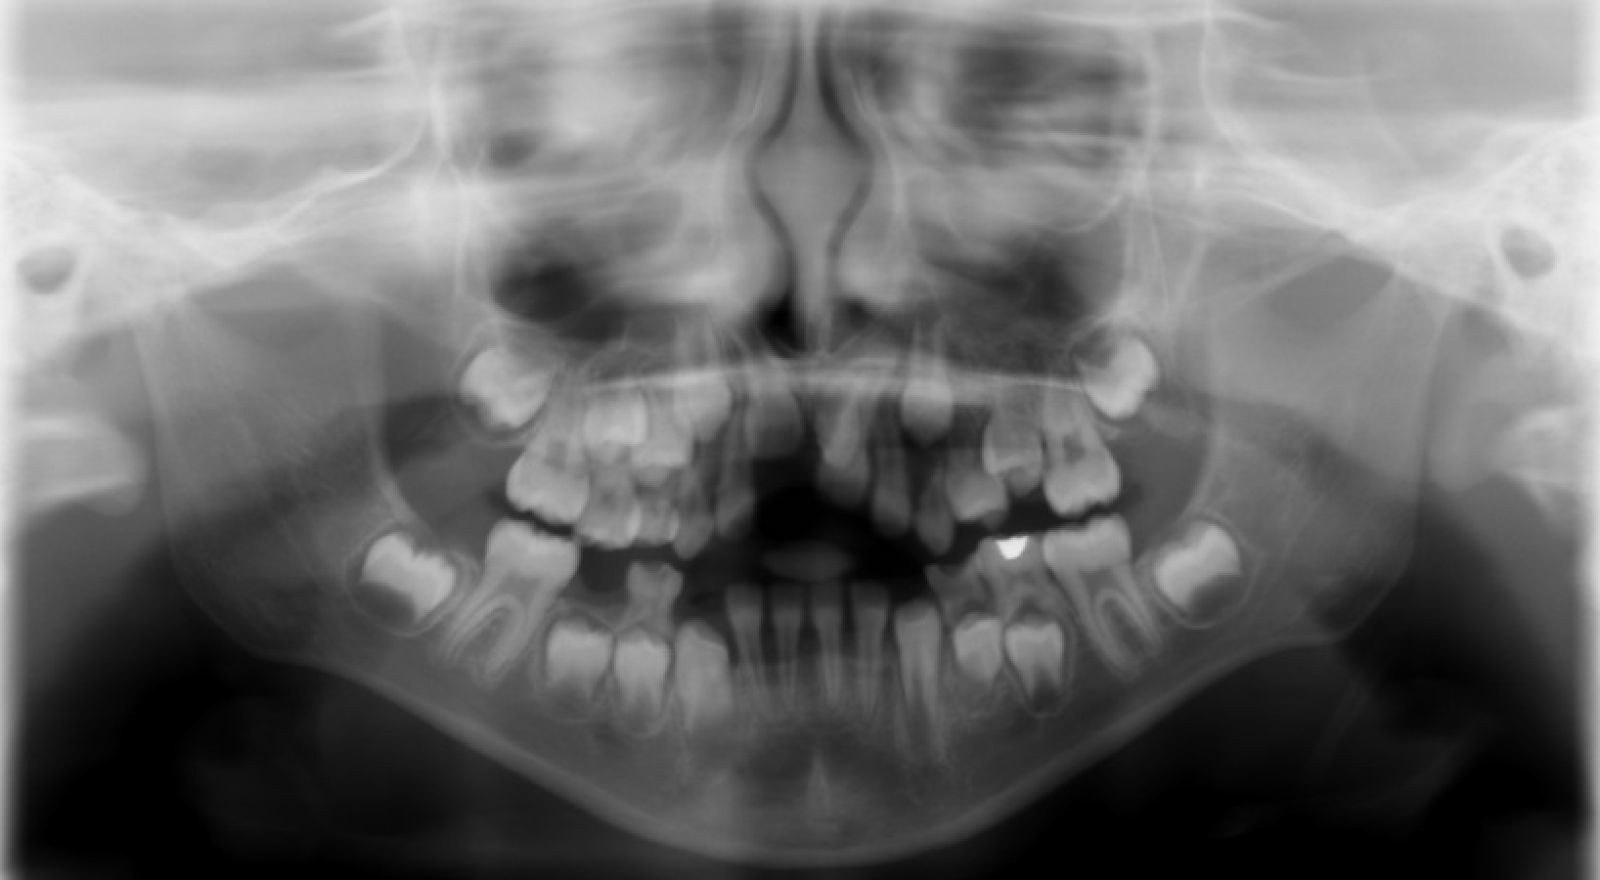

Patient presented to NYUCD to visit the dentist for the first time in 2017. These BWs and PAN were taken then.

Figures 9 & 10: Preoperative bitewings of Right and Left

Figure 11: Preoperative Panoramic image

Unfortunately, due to the amount of dental treatment needed and number of dental visit needed, patient and mother never returned back to NYU dental clinic.

Due to the clinical carious lesions present - 2 BW radiographs were recommended to observe any interproximal carious lesions (also to update the treatment plan that was never fulfilled) and PA#8 to observe the location of mesiodens and any update in eruption of #8 or the mesiodens.

Radiographic Interpretation revealed: Carious lesions in #3-O, #A-O, #14-O, #19-OB, #K-MOD, root tip present in tooth #L, #30-O, Mesiodens present ( disrupting the proper eruption of tooth #8) ***